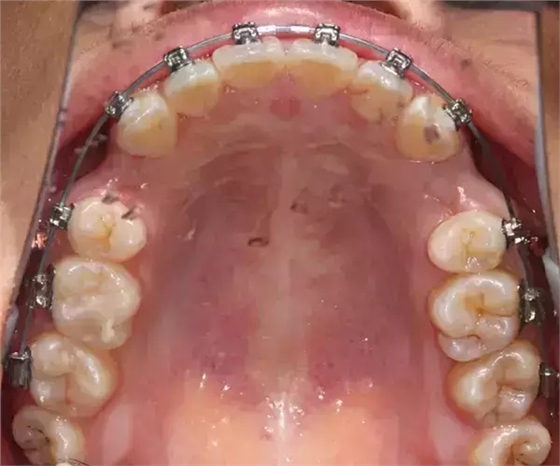

上下牙列擁擠,磨牙尖牙Ⅱ 類關(guān)系,3 度的深覆牙合,上頜中切牙伸長內(nèi)傾拔除上頜雙側(cè)的第一前磨牙,先粘上頜高轉(zhuǎn)矩的自鎖托槽排齊牙列,唇向開展上頜切牙,有一定的覆蓋,粘下頜標準轉(zhuǎn)矩托槽,上頜 1, 2 之間植入種植支抗壓入,同時后牙 5, 6 之間植入種植支抗內(nèi)收前牙,打開咬合關(guān)閉間隙。治療關(guān)鍵:前牙轉(zhuǎn)矩的控制第 1 個月 上頜粘上 Damon Q 高轉(zhuǎn)矩托槽,上 .014 熱激活 NiTi 絲。第 3 個月 上換 .014 x .025 熱激活 NiTi 絲。第 5 個月 上頜基本排齊,覆蓋增大,上換 .017 x .025 NiTi絲,下頜粘托槽,下 .014 熱激活 NiTi 絲。第 7 個月 上 .017 x .025 NiTi 絲加搖椅,下?lián)Q .014 x .025 熱激活 NiTi 絲第 9 個月 上頜換 .019 x .025 NiTi 絲加搖椅,下頜換 .017 x .025 NiTi 絲第 11 個月 下頜換 .019 x .025 加搖椅,上頜 1, 2 之間, 5, 6 之間植入種植釘,下頜出現(xiàn)散隙。第 13 個月 上頜換 .019 x .025ss 加搖椅,前牙種植釘用 Power Chain 壓低前牙(每側(cè) 100g),后牙種植釘關(guān)閉間隙(每側(cè) 150g),下?lián)Q .019 x .025ss,Power Chain 關(guān)閉間隙。第 19 個月 上頜前牙基本壓低到位去除前牙種植釘,繼續(xù)用關(guān)閉間隙,下頜散隙關(guān)閉。

第 22 個月 上頜覆蓋變小,去除 5, 6 之間種植釘,后牙前移關(guān)閉間隙。第 30 個月 患者未配合中線牽引,下中線仍有 1mm 右偏,患者對矯治效果滿意要求拆除,拆除固定矯治器,取模制作壓模保持器。 1.骨性 Ⅱ 類的患者內(nèi)收前牙時需對上頜前牙的轉(zhuǎn)矩進行較好的控制才能獲得良好的面型和唇部形態(tài)。 2.露齦笑的患者治療前要分析其病因是唇、牙齦、牙齒、牙槽骨、上頜骨或多種因素結(jié)合,再制定矯治方案。 3.Ⅱ 類第二分類伴露齦笑的患者的上頜前牙移動軌跡是唇向開展-壓低-整體內(nèi)收。 4.Ⅱ 類第二分類牙齒舌傾比較厲害的情況,上頜中切牙慎用樹脂咬合墊。 5.壓低前牙或控根移動時容易發(fā)生牙根的吸收,需輕力緩慢的移動。